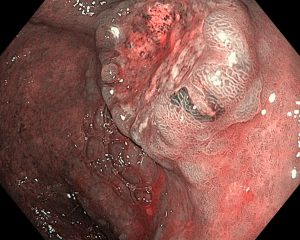

В эндоскопическом атласе обычно представлены изображения и видео, полученные во время процедур, проводимых врачами-эндоскопистами. Эти изображения и видео могут использоваться для обучения студентов медицинских учебных заведений, повышения квалификации медицинских работников, а также для консультации врачей при диагностике и лечении различных заболеваний.